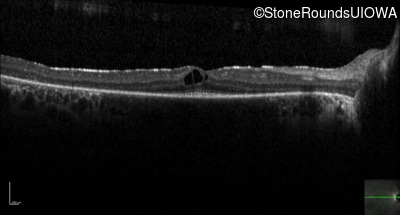

Optical Coherence Tomography - Right -

20/20 -1

Exemplar / OCT Stack